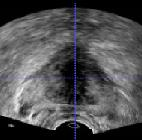

Prostate cancer biopsy benefits from accurate fusion of transrectal ultrasound (TRUS) and magnetic resonance (MR) images. In the past few years, convolutional neural networks (CNNs) have been proved powerful in extracting image features crucial for image registration. However, challenging applications and recent advances in computer vision suggest that CNNs are quite limited in its ability to understand spatial correspondence between features, a task in which the self-attention mechanism excels. This paper aims to develop a self-attention mechanism specifically for cross-modal image registration. Our proposed cross-modal attention block effectively maps each of the features in one volume to all features in the corresponding volume. Our experimental results demonstrate that a CNN network designed with the cross-modal attention block embedded outperforms an advanced CNN network 10 times of its size. We also incorporated visualization techniques to improve the interpretability of our network. The source code of our work is available at https://github.com/DIAL-RPI/Attention-Reg .